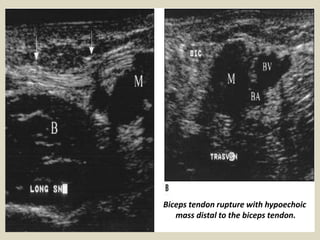

Rupture of the distal biceps tendon

is uncommon and it is usually due to attempting to lift

a heavy weight. Complete ruptures usually cause pain

and a clinically palpable defect so it is not difficult to

diagnose. In complete tears without muscle retraction,

when there is an important soft-tissue swelling with

difficult clinical examination or in partial ruptures,

imaging may be required. The complete rupture of the

tendon produces a defect at the expected location of

the tendon. The gap is filled with hematoma, and the

retracted tendon edge may be visible. Anomalies of

the median nerve can also be demonstrated. We show

a case of iatrogenic neuropathy after venopuncture.

Biceps tendon rupture with hypoechoic

mass distal to the biceps tendon.